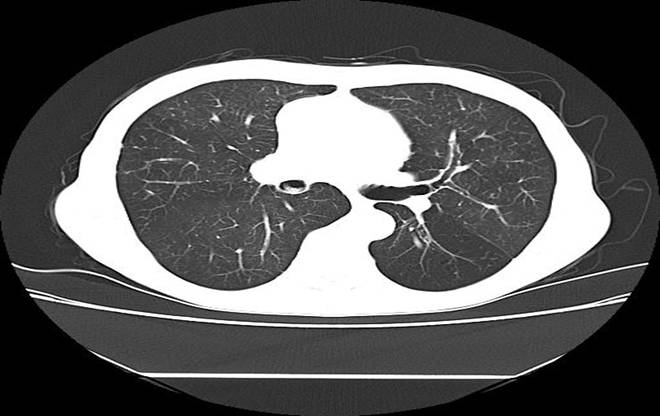

胸部SCT

出院前复查胸部SCT